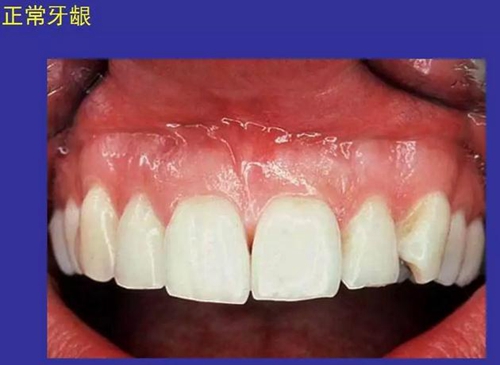

①口腔黏膜(oral mucosa):口腔內(nèi)的濕潤(rùn)襯里

一、口腔黏膜感染性疾病圖示